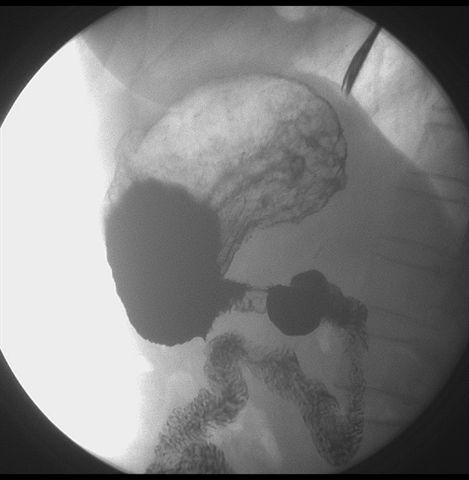

标题: X6872:F,69y,胃部不适。

胃窦至幽门段胃壁僵硬,扩张受限,局部纠集粘破坏,呈杵状。提示溃疡癌变可能性大。

胃窦癌可能性大,建议胃镜活检。钡剂太稀,吃的有点多。

瀑布型胃,胃粘膜那是一个乱,窦部充盈不好,第16幅窦部粘膜反倒又很顺,先定个胃炎胃窦炎胃窦癌待排之类,建议进一步作胃镜检查。

胃窦部见钡池影,局部粘膜紊乱,纠集呈杵状改变,胃壁扩张受限,胃窦癌可能性大,建议胃镜检查.

胃窦占位。大量滞留液?十二指肠球炎?

胃窦部管腔扩张度较差,形态略有改变,胃窦粘膜显示欠佳,胃窦部占位可能性大,结合胃镜活检。

北京肿瘤医院胃镜诊断皮革胃。